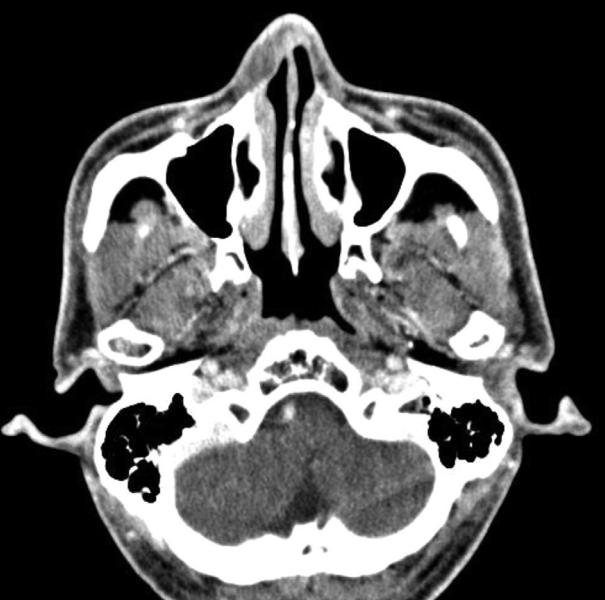

CaseA 58-year-old male patient visited our hospital with a right nasal dorsum swelling. CT scan demonstrated a 1.3×0.5 cm poorly enhanced low attenuation lesion in right nasal ala (Fig. 1). Fine-needle aspiration cytology tests confirmed benign myxoid spindle cell lesions. Surgery was recommended, but the patient refused the operation. Five years later, the patient returned to the hospital because the swelling of the right nose worsened (Fig. 2). MRI demonstrated a 1.7×1.3×1.2 cm T1-weighted image low signal intensity, T2-weighted image high signal intensity, and peripheral enhanced soft tissue lesion in right nasal ala (Fig. 3).

Radiographically, myxomas are usually well-defined ovoid masses with bony destruction or remodeling that show attenuation similar to that of water on CT [2]. On MRI, the tumor exhibits the signal intensity characteristic of fluid [6]. Intraoperatively, most masses are usually identified as glistering gelatinous masses which are oval or spherical in shape [2,4,7]. Histologic features of myxoma include spindled and stellate cells embedded in a fibromyxoid background [2,5,7,8]. Therefore, the definitive diagnosis of myxoma is made by microscopic examination to identify bland spindle cell myxoid lesion [2-6]. The spindled cells of myxoma will stain positively for vimentin and may show some positivity for S-100 protein and muscle-specific actin [2].